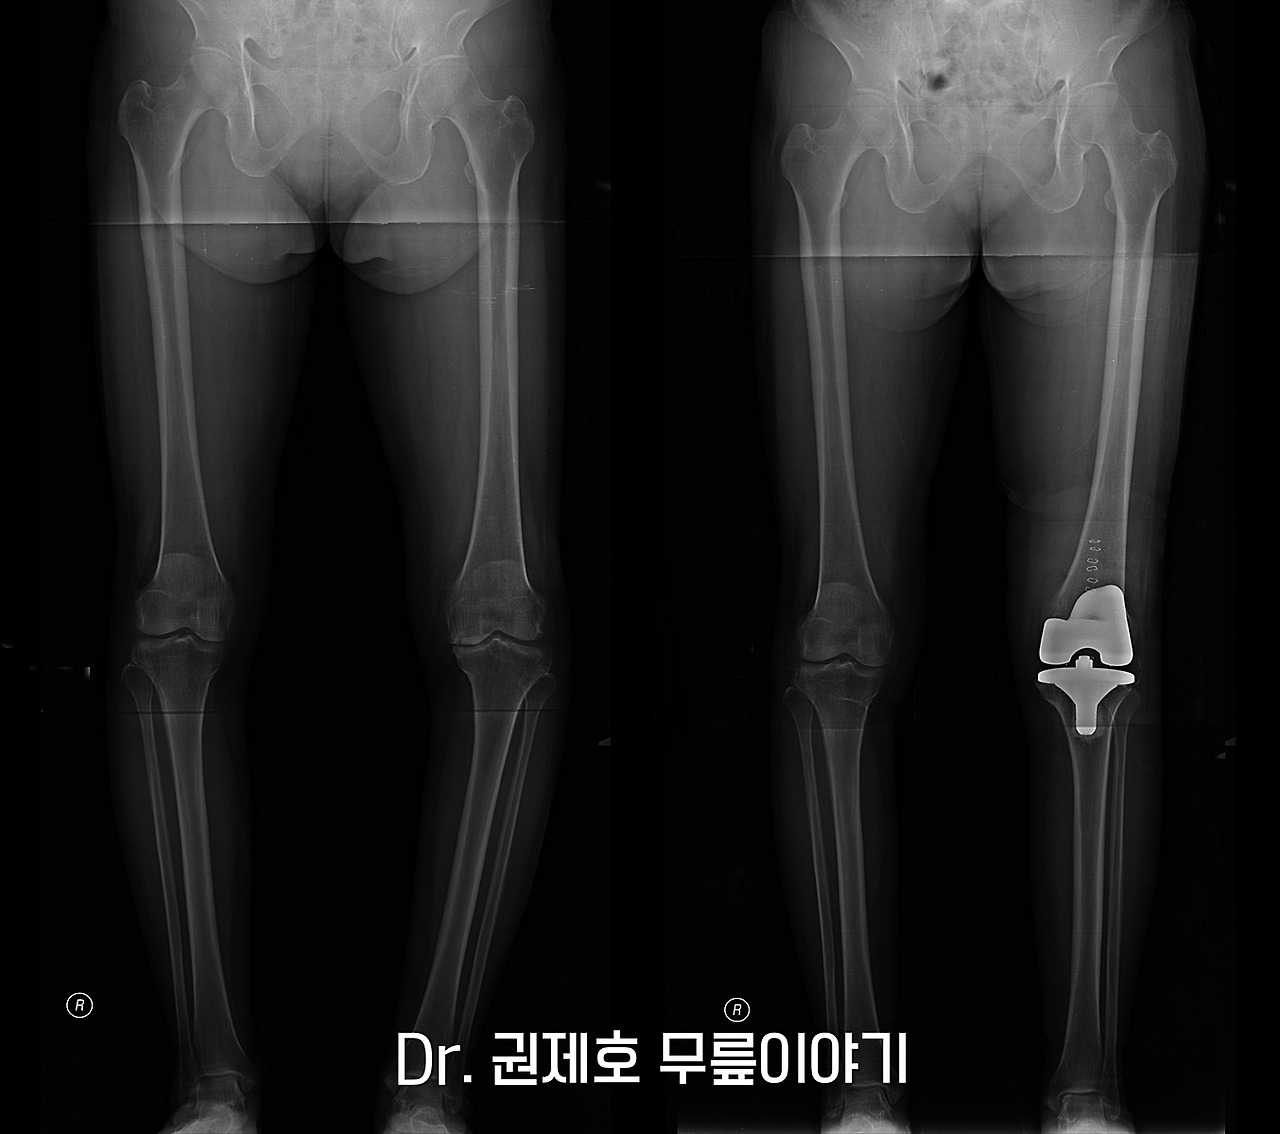

수술은 비교적 빠르게 시행된다. 닮아 없어진 연골을 모두 제거하고 코발트크롬으로 만들어진 인공관절로 닳은 관절을 교체하게 된다. 이 과정에서 하지 정렬 즉, 다리의 열도 같이 맞춰줘야 하며, 관절의 간격도 맞춰야 하는 복잡한 이론이 적용된다. 수술하면서 이 모든 것을 고려해가면서 퇴행성관절염 수술을 한다.

퇴행성관절염 인공관절 수술 과정 (8).jpg

2주 정도가 지나면 자력을 서있을 수 있다. 실을 제거하고 나서 다시 사진을 검사한다.

관절염으로 휜다리가 있는 다리가 인공관절 후 반듯해진 모습을 확인할 수 있다.